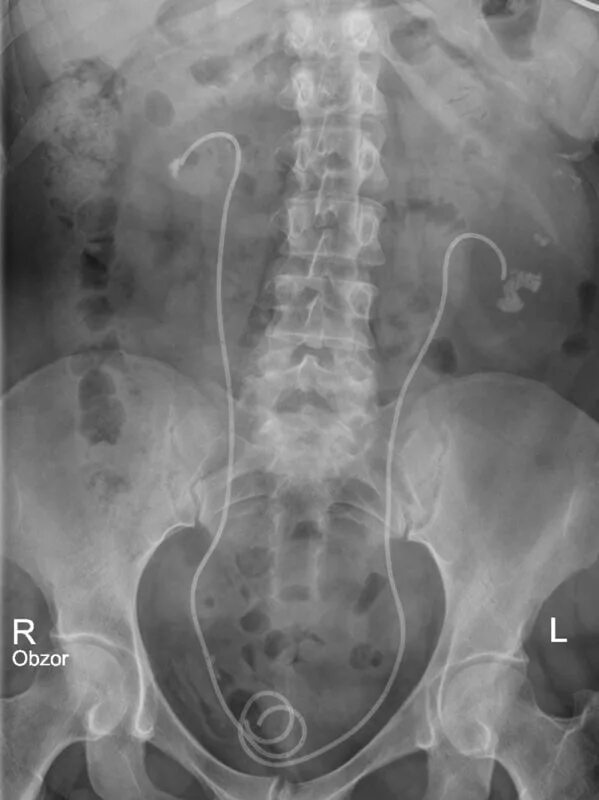

После урографии